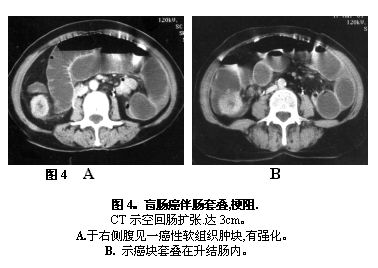

急慢性胃肠道梗阻伴胃肠腔内大量潴留如胃幽门梗阻和单纯性、绞窄性肠道机械性梗阻时,平片、造影诊断均不理想。CT对此确有其优势,它能容易地判断扩张肠腔的程度、部位;区别胃肠腔内潴留液与肠壁组织;直接显示梗阻端胃肠腔内,肠壁内、外造成梗阻的病变,如肿瘤、结石等;也能对机械性与麻痹性肠梗阻做出鉴别;对肠梗阻后的并发症如穿孔、绞窄做出判断。可以预期随着经验的积累,CT将成为胃肠道梗阻时唯一有效的诊断手段(图4AB)